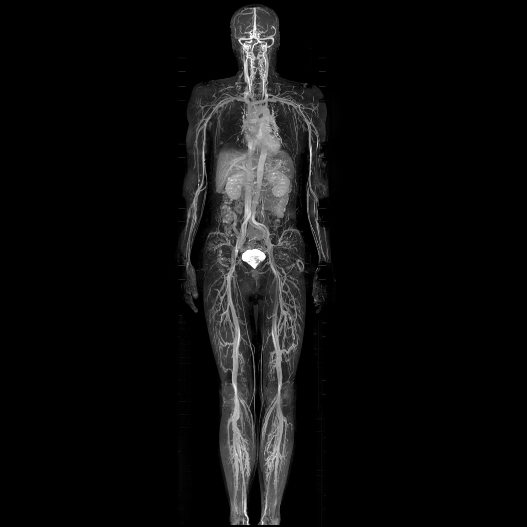

04.Advanced 3T MRI

Whole Body Scan

Whole body clarity.

Personalised for you.

Every detail matters.